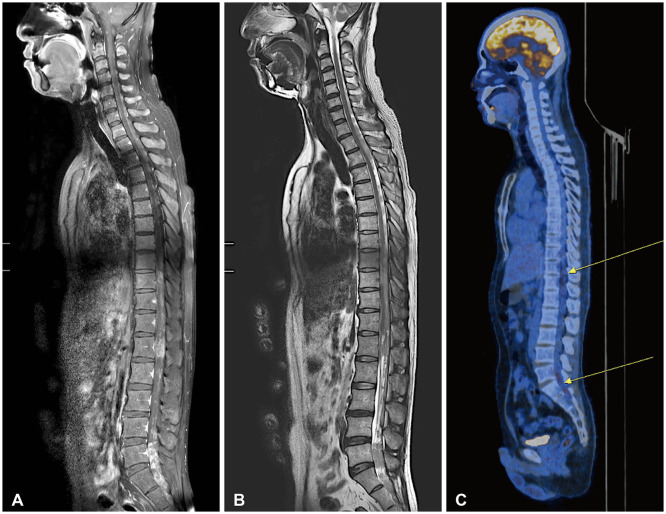

室管膜瘤是一种罕见的成人肿瘤,起源于中枢神经系统的室管膜细胞,主要发生在脑室或脊髓中央管。在这篇文章中,我们报告一个39岁的男性患者,在头部外伤后偶然发现了广泛的室管膜瘤。MRI表现为弥漫性脑脊膜浸润性病变,伴双侧多脑沟、基底池、桥小脑角、小脑叶。它还显示沿整个脊髓的多结节增强T1低T2高信号强度病变。右侧颞叶病变肿瘤活检后,病理诊断为典型室管膜瘤(WHO分级2级)。患者接受放疗和化疗,术后2年病情稳定。本报告提示,在考虑颅内和椎管间隙广泛病变的鉴别诊断时,也应考虑室管膜瘤。

Ependymoma is a rare adult tumor that originates from ependymal cells of the central nervous system, primarily occurring in the cerebral ventricles or the central canal of the spinal cord. In this paper, we report a case of extensive leptomeningeal seeding of ependymoma of a 39-year-old male patient, in whom the tumor was found incidentally after head trauma. The MRI exhibited diffuse leptomeningeal infiltrative lesions along with bilateral multiple cerebral sulci, basal cisterns, cerebellopontine angle, cerebellar folia. It also showed multinodular enhancing T1 low T2 high signal intensity lesions along the whole spinal cord. After the tumor biopsy at right temporal lesion, pathologic diagnosis was classic ependymoma (WHO grade 2). The patient has undergone radiation therapy and chemotherapy, and is currently maintaining a stable condition two years after surgery. This report suggests that when considering the differential diagnosis of extensive lesions both in the intracranial and intraspinal space, ependymoma should also be considered.